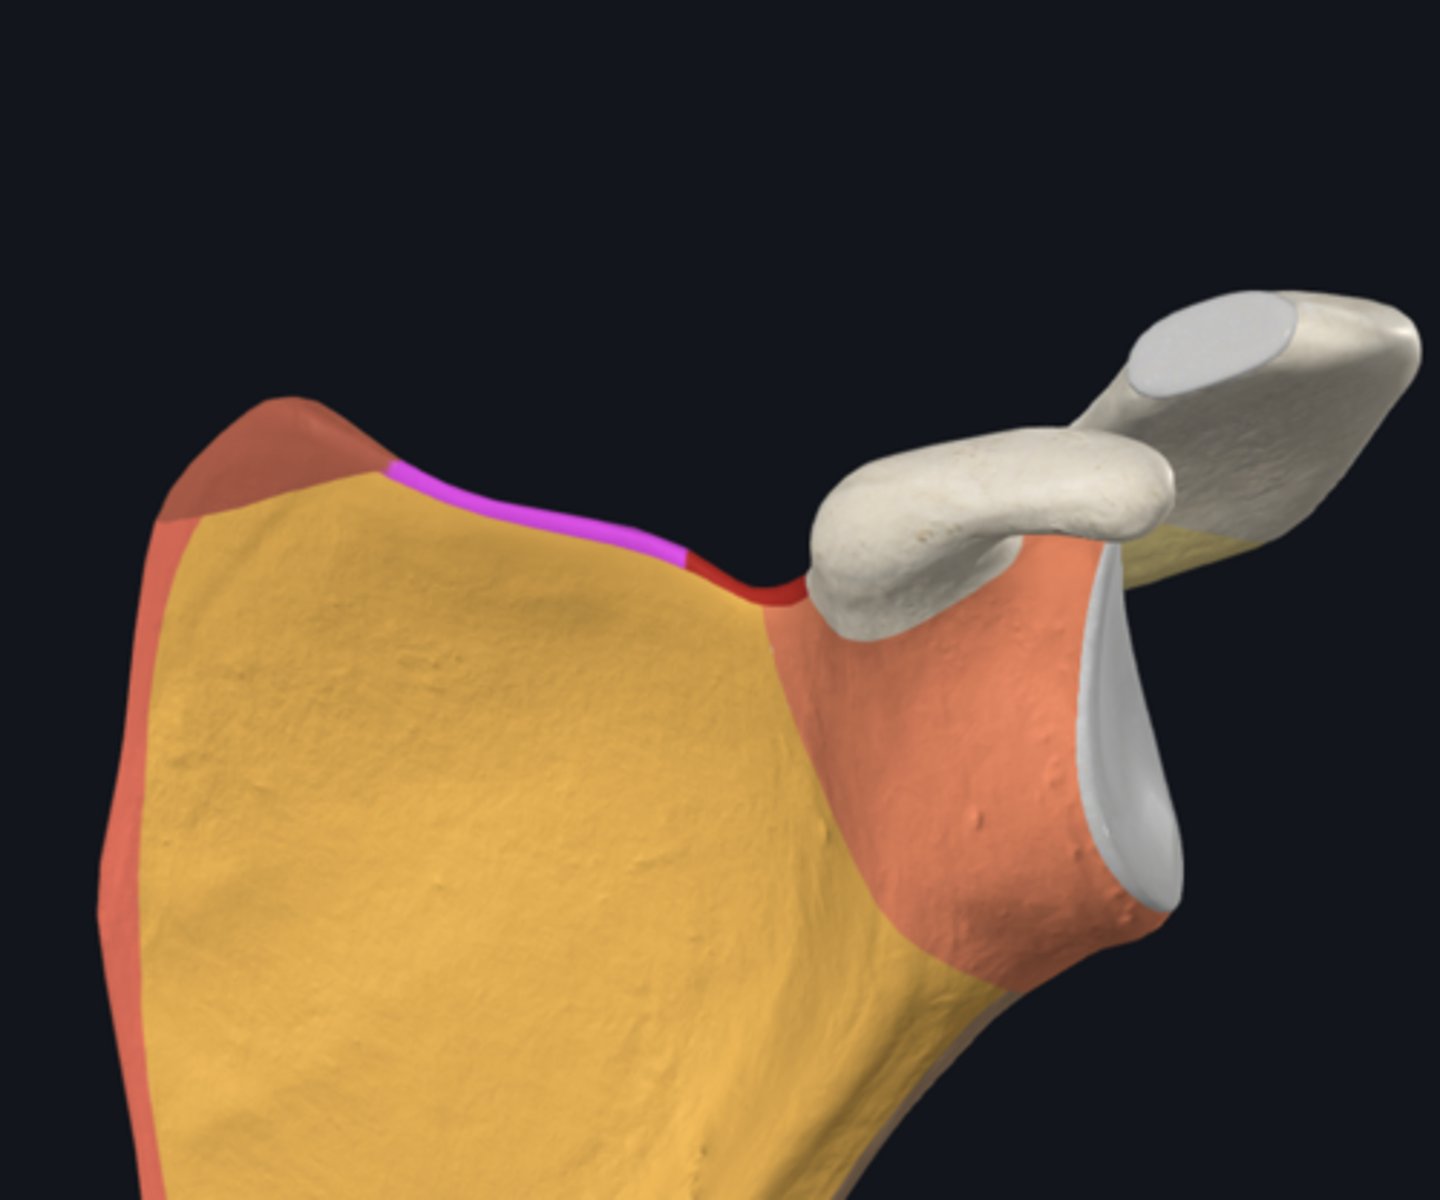

Acromion

Coracoid process

posterior surface of scapula

acromial angle

glenoid fossa

infraglenoid tubercle

infraspinous fossa

spine of scapula

supraspinous fossa